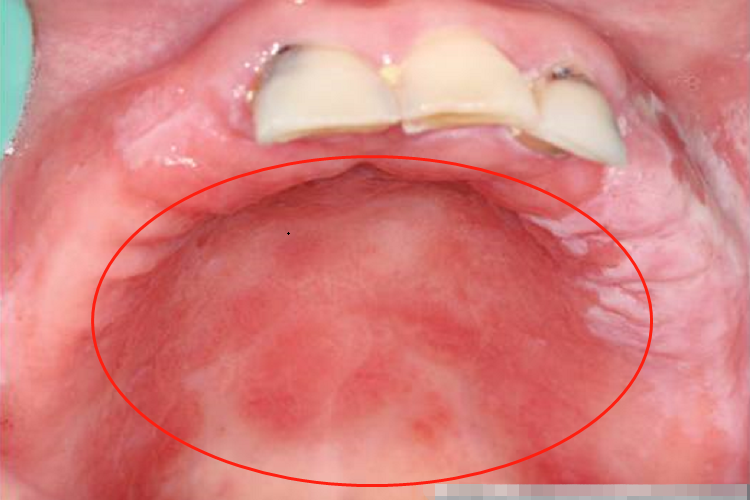

慢性红斑型念珠菌病又称义齿性口炎,表现为损害部位常在上颌义齿腭侧面接触的腭、龈黏膜,女性患者多见。黏膜呈亮红色水肿,或有黄白色的条索状或斑点状假膜。